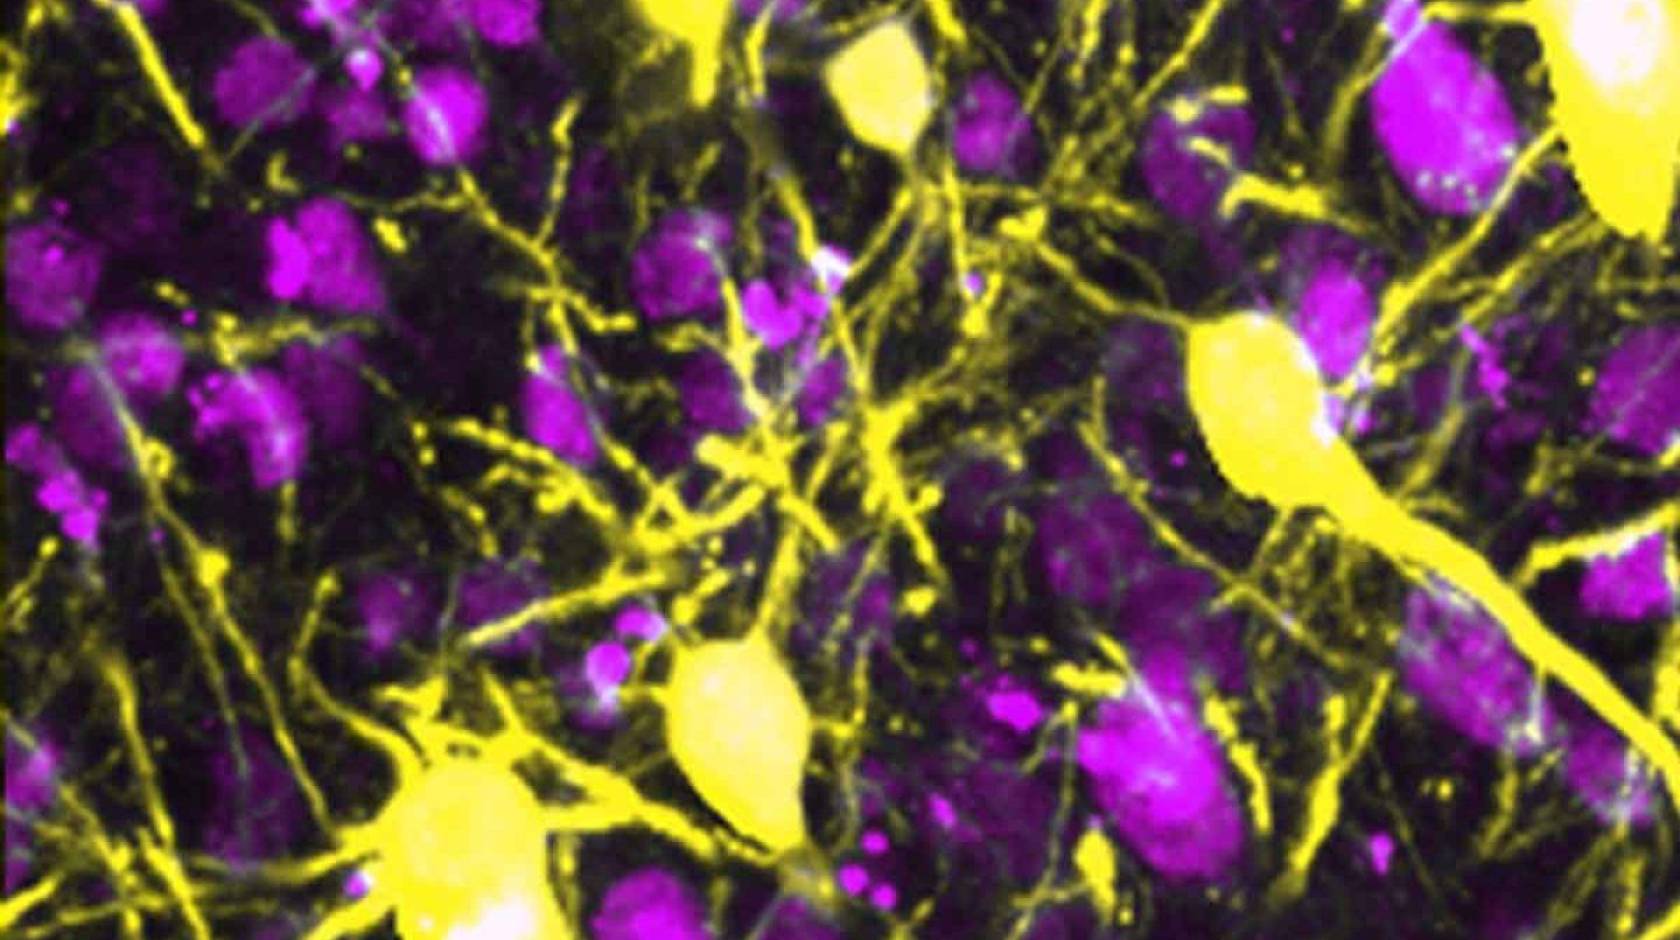

The brain’s neurons (yellow) connect with one another using a vast network of neural wires, called neurites.

Ray Swanson’s team discovered that inflammation — a consequence of diseases like Alzheimer's and stroke — destroys these wires but spares the neurons.

The mice did struggle to move, but when the researchers looked at their brain tissue under a microscope, they were surprised to see that only the neurites had withered away, leaving the neurons isolated like stars in the night sky. The loss of these connections was enough to rob the mice of some of their motor coordination.

In laboratory animals treated with increasing doses of the inflammatory molecule, S100β, the healthy web of neurites slowly deteriorates, leaving the neurons disconnected.